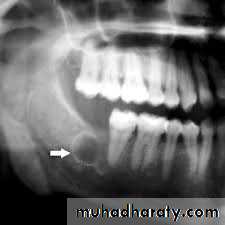

3. Globulomaxillary cysts:G. cyst are epithelial lined sacs formed at the junction of the globular and maxillary processes between the lateral incisor and canine teeth They usually cause a divergence of the roots of these teeth and appears as a pear-shaped radiolucency's on x-ray film. As is true with other cysts of the oral-cavity, they become secondarily infected and undergo acute inflammatory changes. Treatment is surgical and consists of careful excision.